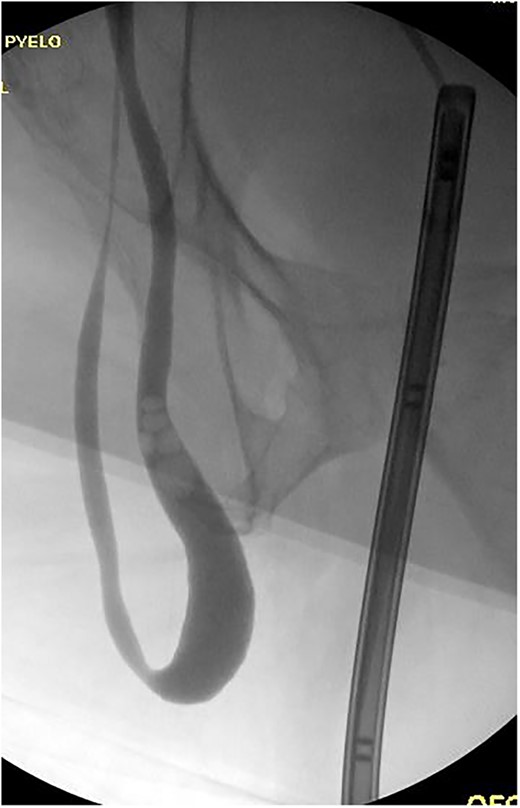

The patient was taken to the operative suite where he underwent cystoscopy, retrograde pyelogram and temporary ureteral stent placement (Fig. 2). Right inguinal exploration was performed, and the patient was found to have a large direct hernia containing abundant adipose tissue. The ureter and cord structures were identified. Adipose tissue was amputated with an energy device. The ureter was reduced into the retroperitoneum. The hernia was then repaired with modified Lichtenstein technique using macroporous polypropylene mesh. Retrograde pyelogram was repeated at completion of the hernia repair following stent removal. A serpiginous course of the ureter was noted without obstruction (Fig. 3). He was observed overnight and discharged home the following day. Post-operative course was uneventful.

Retrograde pyelogram following hernia repair with tortuous path of the ureter.